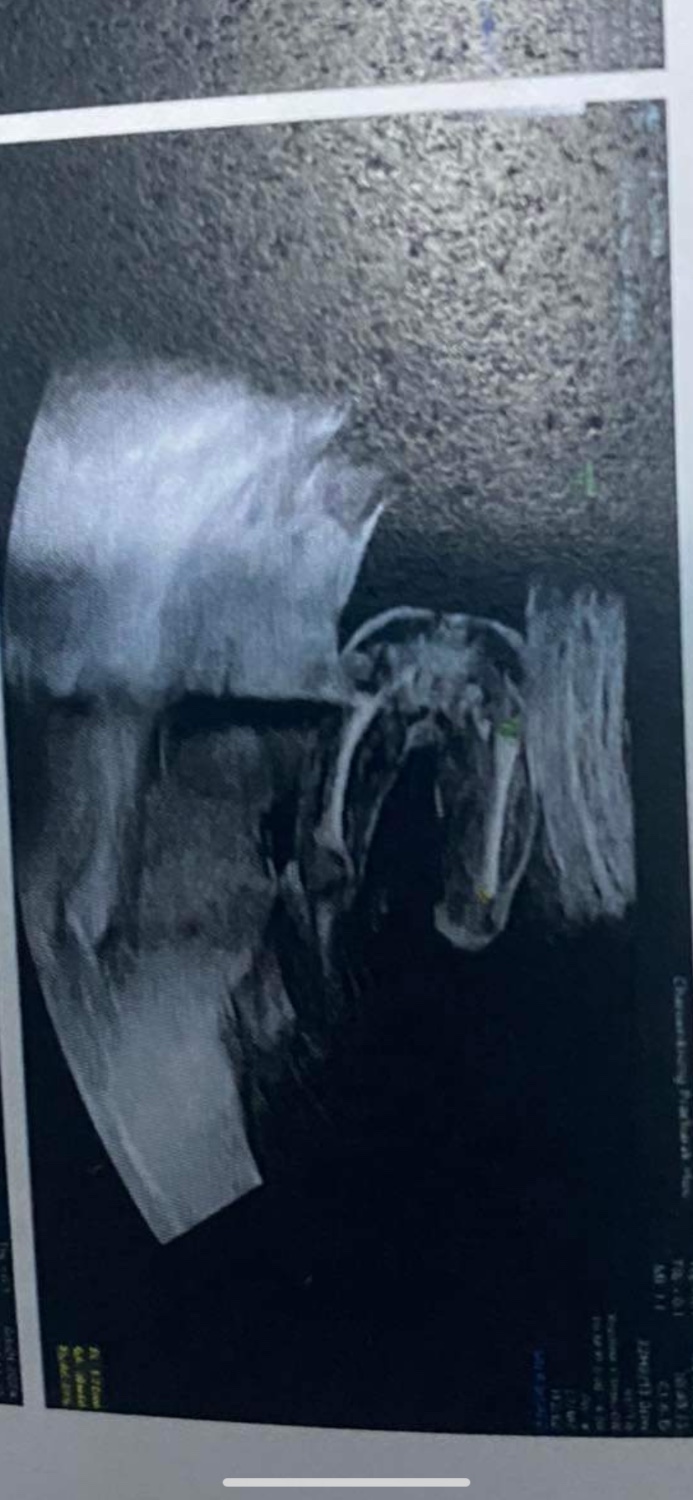

ช่วยดูหน่อยค่ะน้องเป็นเพศไหนคะ

เพศลูก